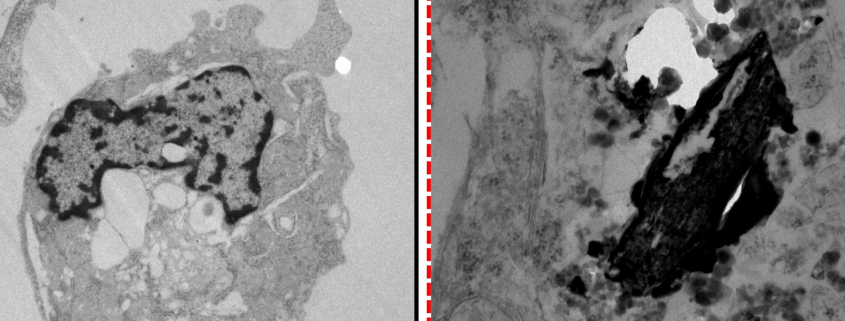

Investigación desarrollada en el Universidad de Murcia (UMU) recibió el premio “Joaquín Moreno Clavel”concedido por la Real Academia de Farmacia de la Región de Murcia en el ámbito de medio ambiente y salud, por su excepcional contribución al conocimiento de los efectos de la contaminación ambiental sobre las células cardíacas. La obra premiada, titulada «Análisis de los principales mecanismos proinflamatorios en patología cardiovascular mediante estimulación con lipopolisacáridos y partículas urbanas en cardiomiocitos auriculares de ratón»forma parte de la tesis doctoral de Darío Mandaglio ColladosEstudiante predoctoral del programa de Doctorado en Ciencias de la Salud de la Universidad de Murcia. Este estudio demuestra el potencial efecto inflamatorio que la contaminación ambiental y las partículas urbanas ejercen sobre los cardiomiocitos, las células responsables de la función contráctil del corazón. El Premio Joaquín Moreno Clavel se concedió conjuntamente con el trabajo de Miguel Motas, investigador de la UMU.

La investigación de Mandaglio aporta nueva evidencia sobre los mecanismos proinflamatorios implicados en la patología cardiovascular, fortaleciendo la relación entre la exposición a contaminantes ambientales y el desarrollo o empeoramiento de enfermedades del sistema cardiovascular, una de las principales causas de muerte en todo el mundo.